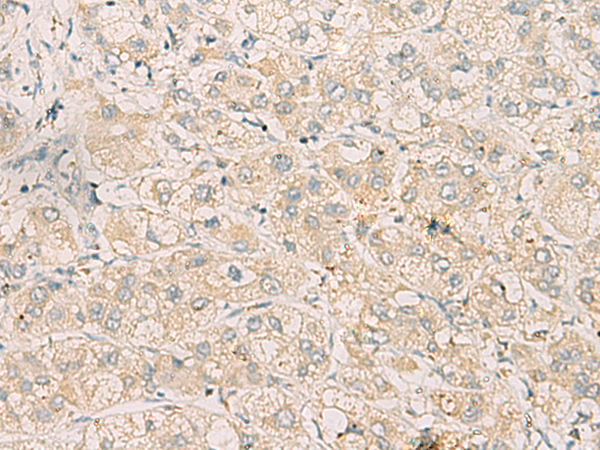

分类: 科研抗体货号: P11104别名: YC1, MSSP, SCR2, HCC-4, MSSP-1, MSSP-2, MSSP-3, C2orf12应用: IHC反应种属: Human, Mouse, Rat